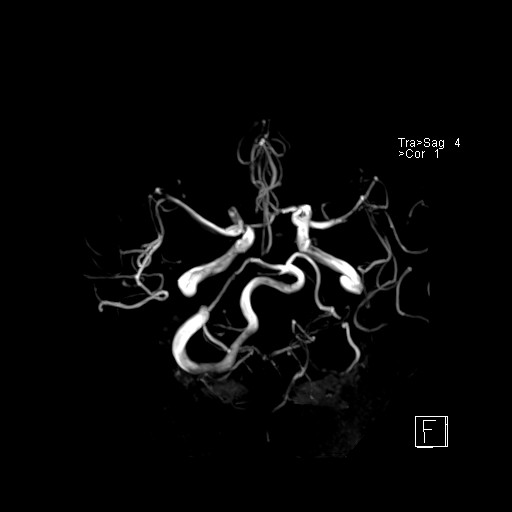

239716 - VILLANUEVA, WILLIAM A. - Number 4 |

|

239716 - VILLANUEVA, WILLIAM A. - Number 4 |